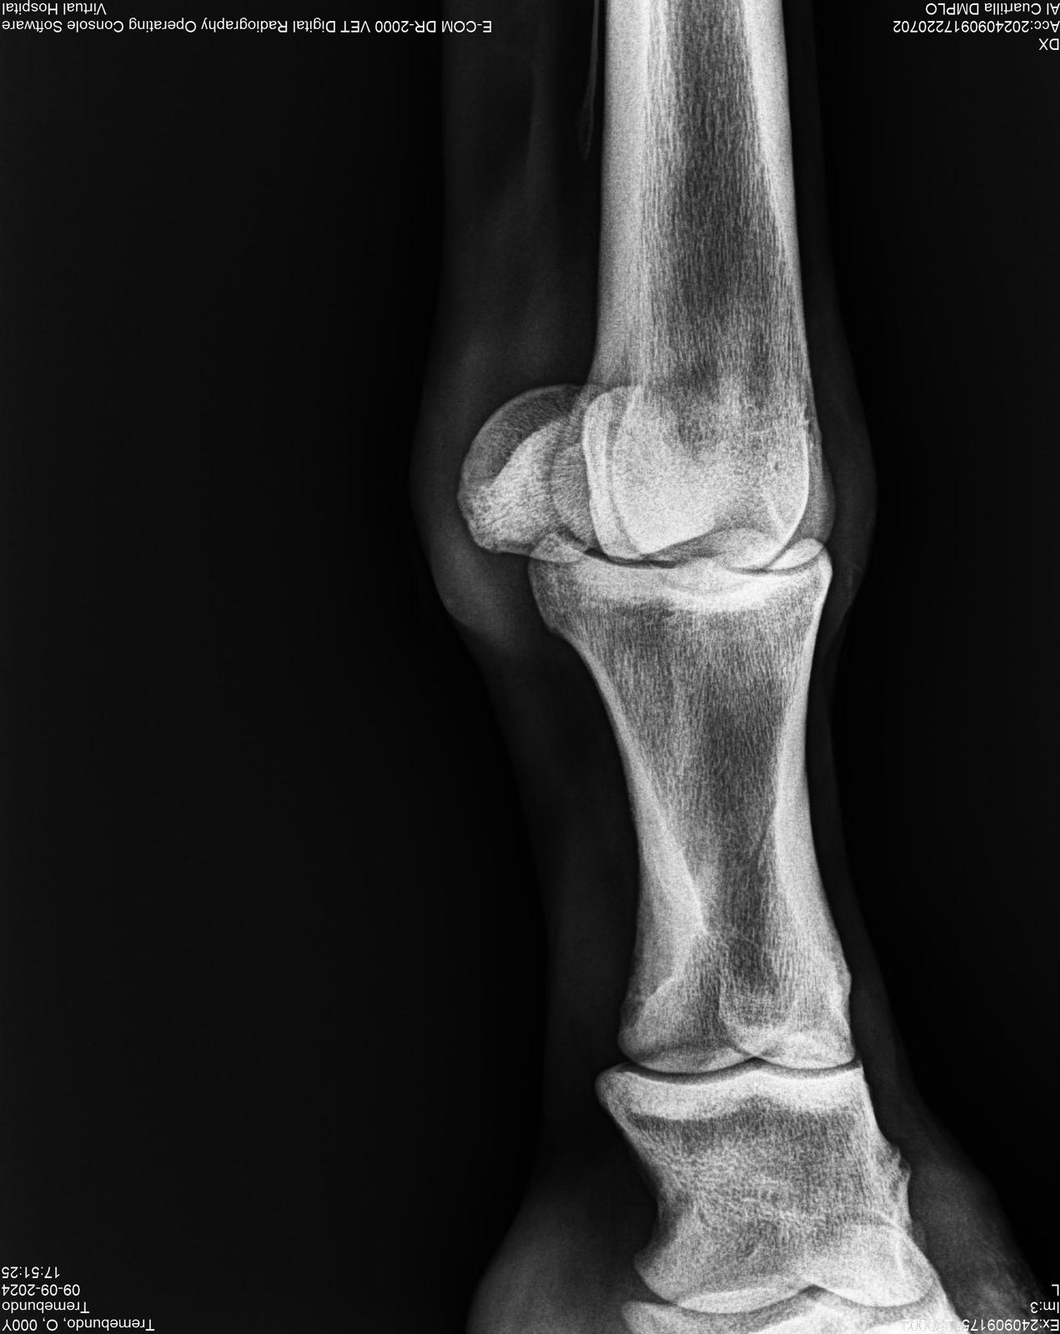

LOTE 37, TREMEBUNDO

Identificador: #291140-

Generacion 2022